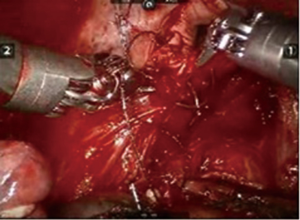

After inserting the ports, the robot was docked. We performed the approach using the three-arm video-assisted thoracic surgery (VATS)-based technique described elsewhere (14). The anterior arm was inserted through a utility incision (Figure 1). The four-arm VATS-based approach was used only in one patient who underwent isolated bronchial resection. The use of V-loc sutures was preferred in the last six cases (Figure 2). As a rule, a prostate bulldog clamp was used to stabilize the first suture (Figure 3). We routinely covered the anastomosis or suture line with pleura, pericardial fatty tissue or rarely with thymus (Figure 4).